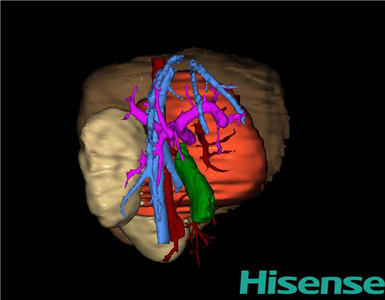

术前三维重建及手术方案设计:

通过调节窗宽窗位调整CT序号,对肿瘤,肝实质,胆囊,下腔静脉,肿瘤,肝动脉、门静脉及肝静脉等进行三维重建;系统自动计算肿瘤体积和肝脏体积。

模拟手术操作,自动计算切除肿瘤体积。肝脏体积为573.4ml,肿瘤体积为375.6ml,肿瘤体积为肝脏体积的65.5%,通过比对3-4岁正常肝脏体积为522.63±121.24 ml,通过术前模拟手术,精准判断切除后剩余肝脏体积能耐受,避免肝衰竭发生。

根据手术规划系统提供最优虚拟肝切除步骤解剖沿降结肠外侧切开侧腹膜,切开肾周脂肪囊,显露整个肾脏,见肿瘤位于整个肾脏,约20×15×10cm大小,质地硬,肿物下极包膜破裂并血肿形成。与胰腺、脾脏及降结肠粘连紧密,下极包绕肠系膜上动脉,无法分离并切除,遂决定仅行活检术。在肿物外侧电刀切取约1*1cm大小肿物,防止凝胶海绵1块1-0丝线缝合肿物。检查无活动性出血,清点纱布器械无误,依次缝合腹壁各层。手术顺利,麻醉满意,出血不多,未输血,术后病人先进入麻醉恢复室,苏醒后回病房。术后标本送术中冰冻病理检查,结果回示:小圆细胞恶性肿瘤。手术时手术者可开启Hisense CAS系统手势控制功能,对肿瘤的解剖结构进行实时、全方观察、评估,起到术中导航作用。

术前三维重建:

重建图片